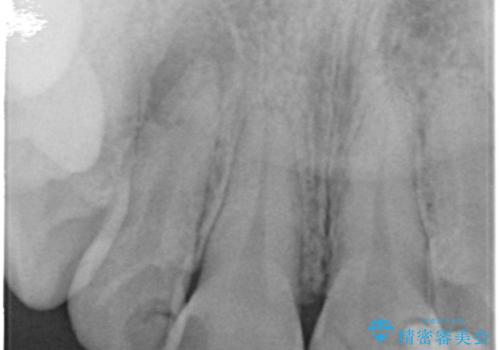

精査したところ、右上の側切歯(右上2)は神経が死んで変色しており、左上の側切歯と犬歯の間に2mm程度の隙間を認めました。

矯正せずに早く治したいという強いご希望により、セラミッククラウンによる補綴治療(上顎両側2の2本)を行いました。

- ¥396,000 (根管治療・土台×1本、仮歯・クラウン×2本) ※税込費用は治療当時の料金となります